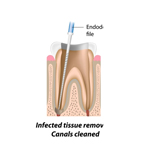

DEVITALIZZAZIONE

La devitalizzazione e' un'operazione odontoiatrica che prevede la distruzione e la successiva rimozione della polpa di un dente; e' un intervento di salvataggio in quanto ne esclude l'estrazione.

Viene eseguita quando la polpa, tessuto ricco di terminazioni nervose e vasi sanguigni, si infiamma, si infetta o viene irrimediabilmente compromessa da processi cariogeni estesi, traumi od altri disturbi dentali gravi. La devitalizzazione include anche la sigillazione (otturazione) del canale pulpare con speciali cementi e materiali biocompatibili, tali da impedire un'eventuale, possibile, diffusione batterica nelle sedi circostanti.